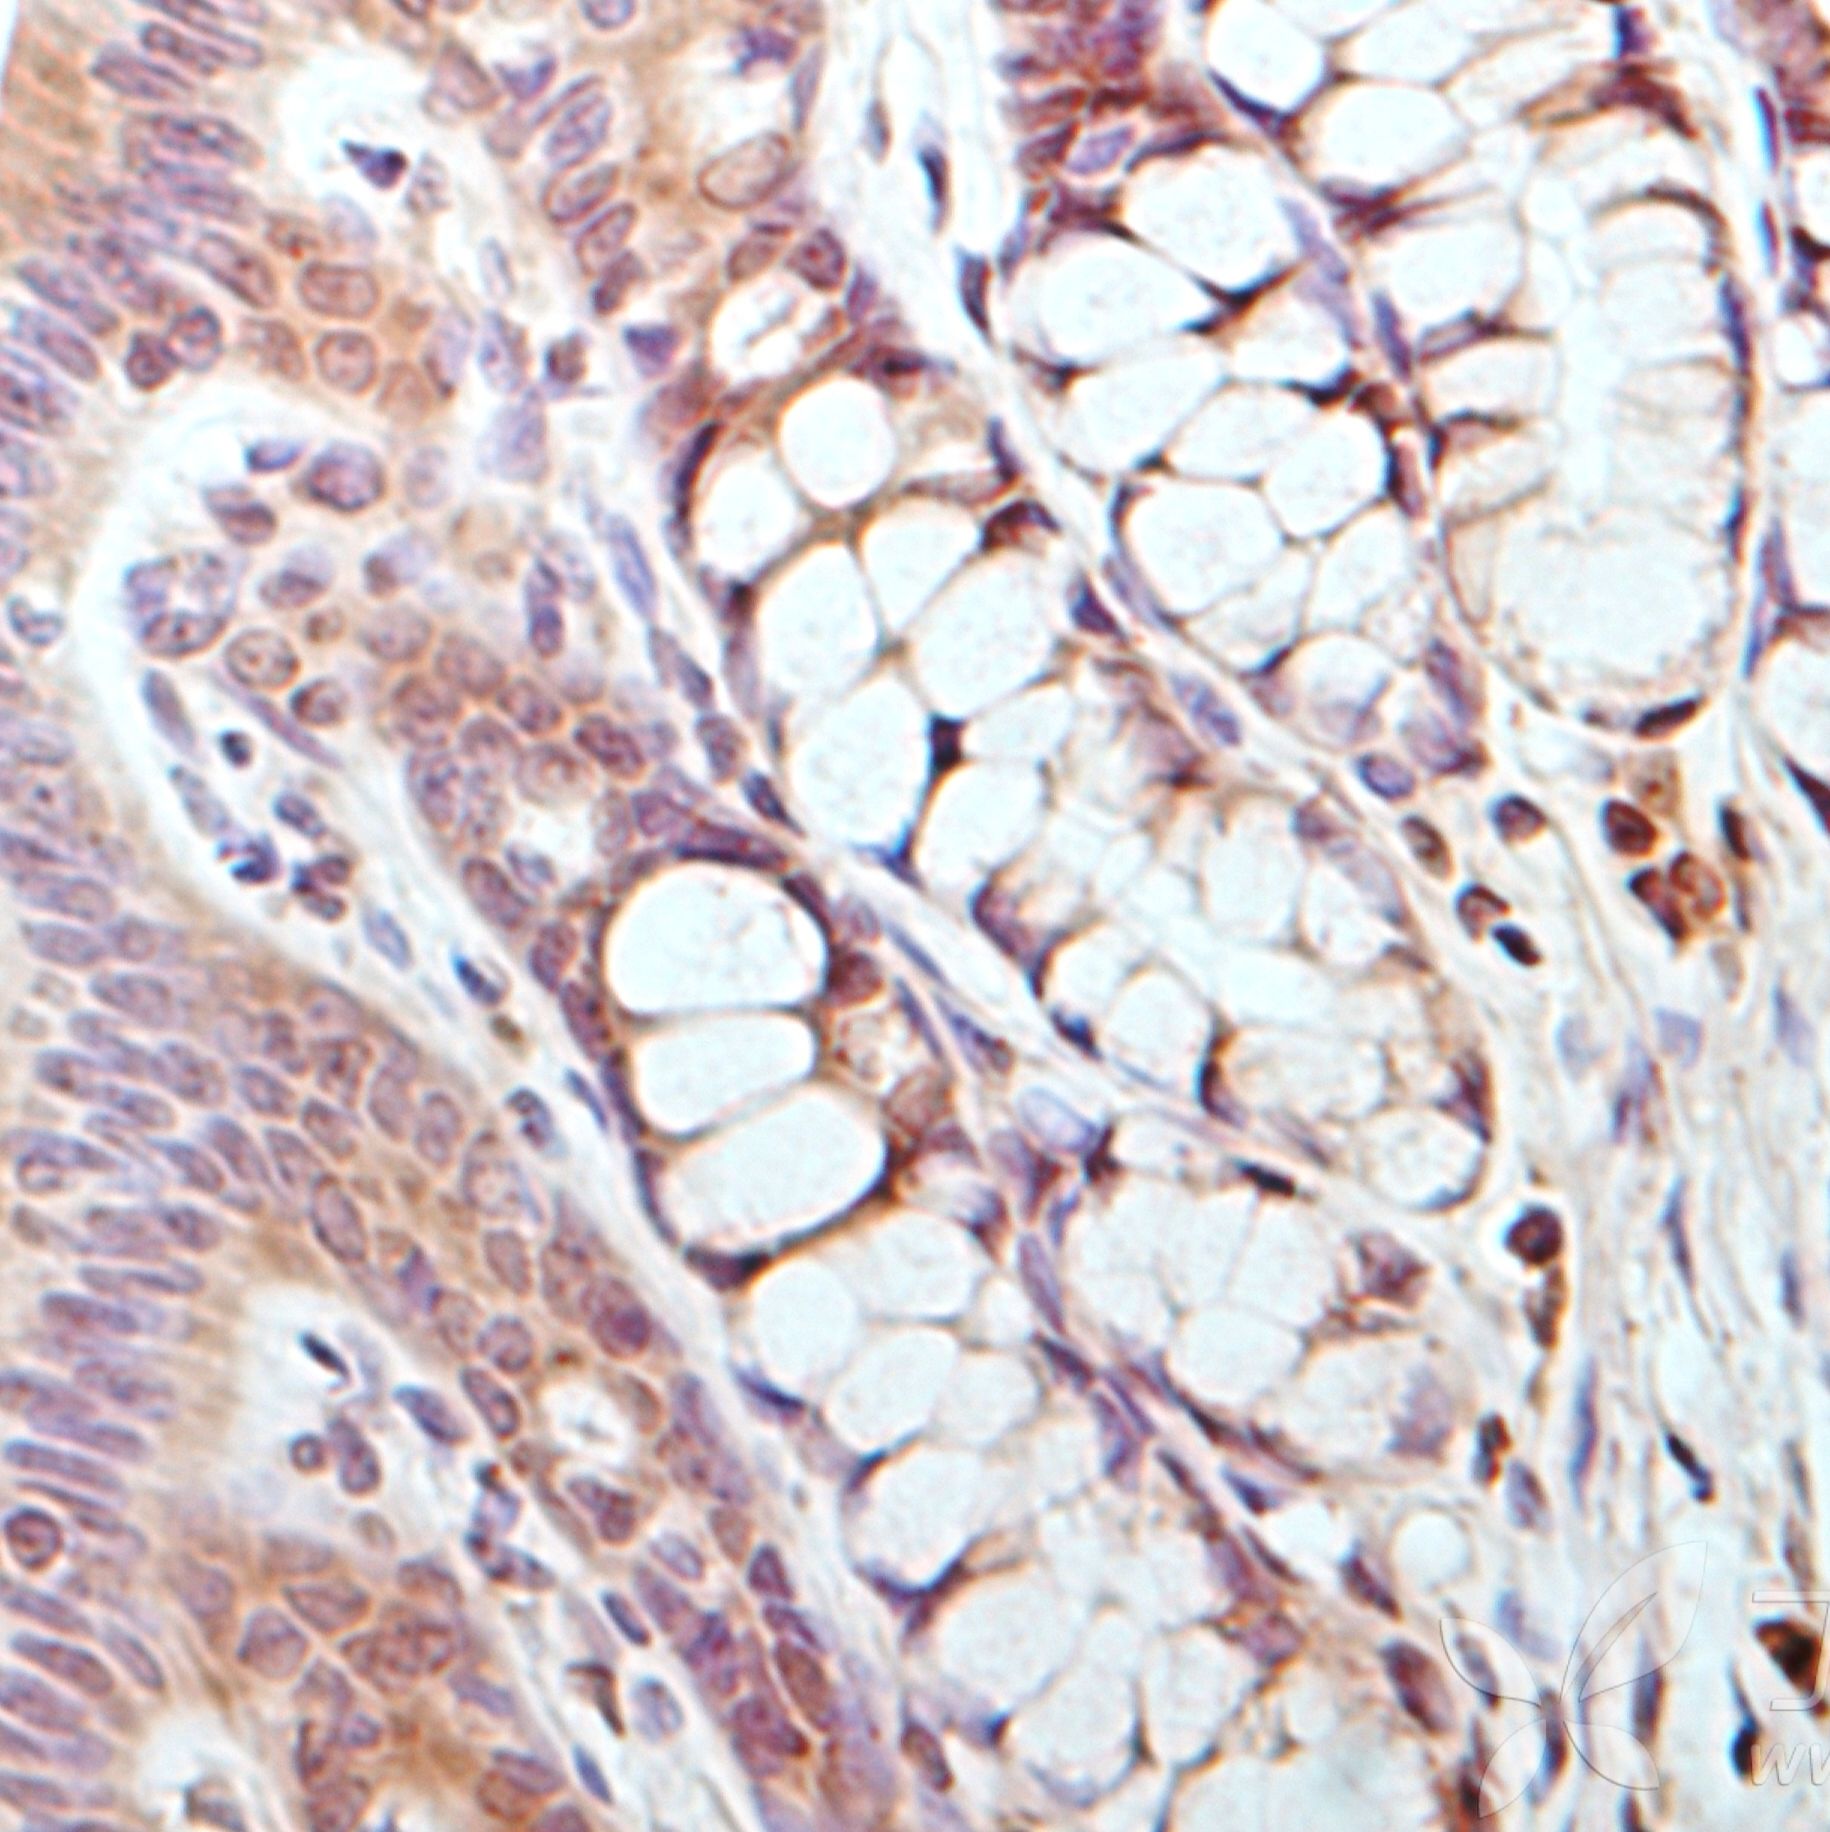

免疫组化检测

免疫组化检测项目及说明 序号 项目名称 说明 1 蜡块 常规 皮肤、细胞、脑定位 EDTA脱钙 (1*2cm左右) EDTA脱钙 ( 1*1.5cm左右) EDTA脱钙 (1*1cn左右) 甲酸脱钙 (1*2cm左右) 甲酸脱钙 ( 1*1.5cm左右) 甲酸脱钙 (1*1cn左

地区:北京服务名称:免疫组化